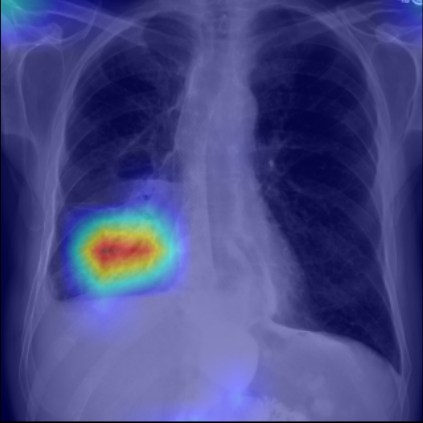

Refer to caption

Figure 5: Visualization of attention map in PLAN on MS-CXR. The red boxes indicate the corresponding ground truth of grounding. Highlighted pixels represent higher activation weights correlating specific words with regions in the image.

IV-B1 Phrase Grounding

Phrase grounding associates textual phrases (e.g., disease descriptions or anatomical terms) with corresponding regions in medical images, offering precise diagnostic insights and enhancing model interpretability. Table II presents the phrase grounding results on the MS-CXR dataset. Using the Contrast-to-Noise Ratio (CNR) [27] as the evaluation metric, PLAN achieved the highest CNR across eight disease categories, outperforming MGCA and PRIOR. Heatmaps generated with Grad-CAM (Figure 4) further illustrate PLAN’s ability to accurately localize lesion sites and align disease-related phrases with image regions. Additional comparisons with baseline methods can be found in Figure 5. These findings highlight PLAN’s superior precision and interpretability in phrase grounding tasks.